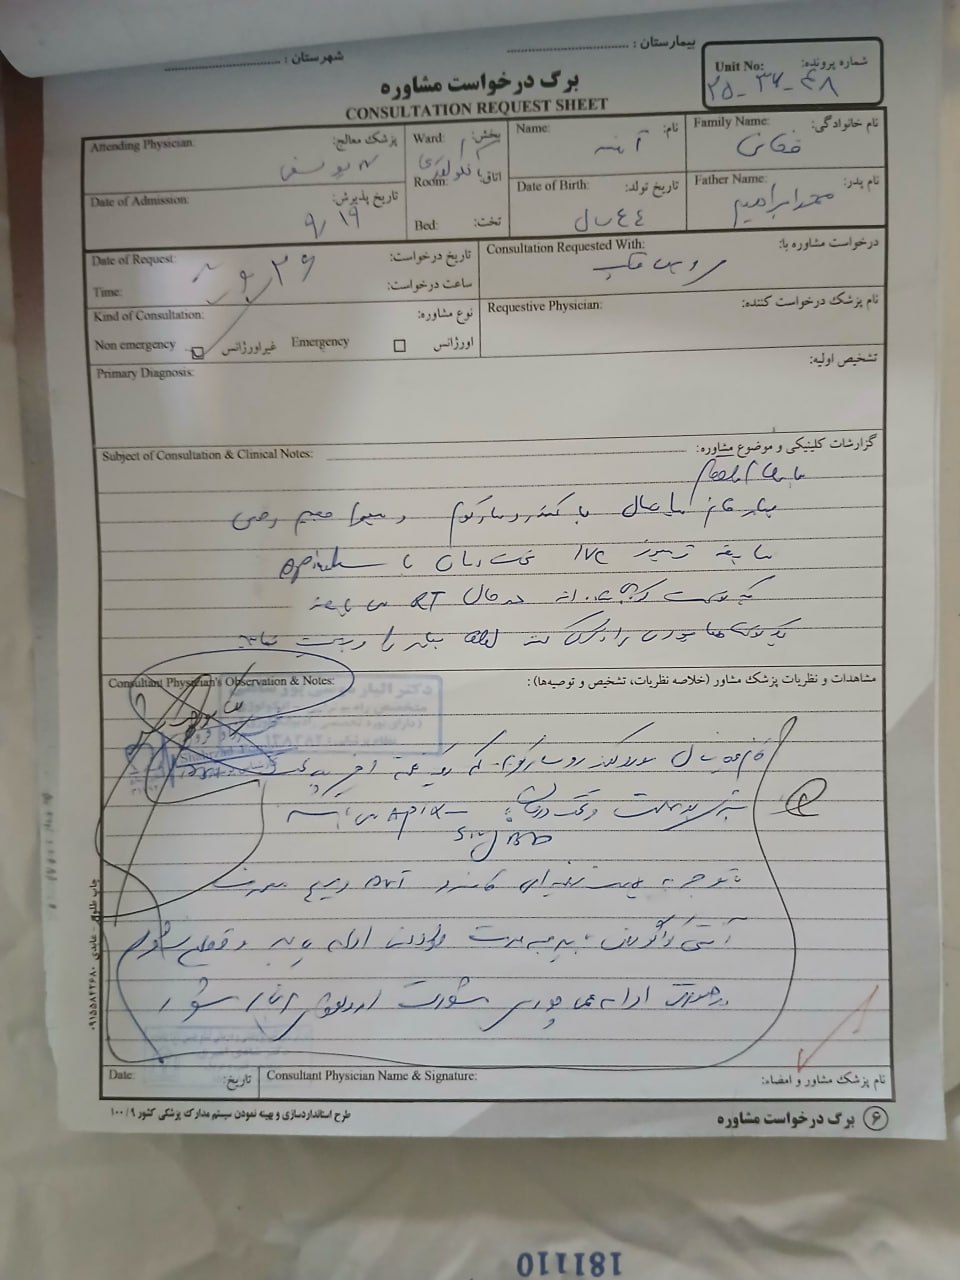

(تصویر مربوط به این مراجعه نیست) Other:

(تصویر مربوط به این مراجعه نیست) Other:

(تصویر مربوط به این مراجعه نیست) Other:

(تصویر مربوط به این مراجعه نیست) Other:

(تصویر مربوط به این مراجعه نیست) Other:

(تصویر مربوط به این مراجعه نیست) Other:

(تصویر مربوط به این مراجعه نیست) Other:

(تصویر مربوط به این مراجعه نیست) Other:

(تصویر مربوط به این مراجعه نیست) Other:

(تصویر مربوط به این مراجعه نیست) Other:

(تصویر مربوط به این مراجعه نیست) Other:

(تصویر مربوط به این مراجعه نیست) Other:

(تصویر مربوط به این مراجعه نیست) Other:

(تصویر مربوط به این مراجعه نیست) Other:

(تصویر مربوط به این مراجعه نیست) Other:

(تصویر مربوط به این مراجعه نیست) Other:

(تصویر مربوط به این مراجعه نیست) Other:

(تصویر مربوط به این مراجعه نیست) Other:

(تصویر مربوط به این مراجعه نیست) Other:

(تصویر مربوط به این مراجعه نیست) Other:

(تصویر مربوط به این مراجعه نیست) Other:

(تصویر مربوط به این مراجعه نیست) Other:

(تصویر مربوط به این مراجعه نیست) Other:

(تصویر مربوط به این مراجعه نیست) Other:

(تصویر مربوط به این مراجعه نیست) Other:

(تصویر مربوط به این مراجعه نیست) Other:

(تصویر مربوط به این مراجعه نیست) Other:

(تصویر مربوط به این مراجعه نیست) Other:

(تصویر مربوط به این مراجعه نیست) Other:

(تصویر مربوط به این مراجعه نیست) Other:

(تصویر مربوط به این مراجعه نیست) Other:

(تصویر مربوط به این مراجعه نیست) Other:

(تصویر مربوط به این مراجعه نیست) Other:

(تصویر مربوط به این مراجعه نیست) Other:

(تصویر مربوط به این مراجعه نیست) Other:

(تصویر مربوط به این مراجعه نیست) Other:

(تصویر مربوط به این مراجعه نیست) Other:

(تصویر مربوط به این مراجعه نیست) Other:

(تصویر مربوط به این مراجعه نیست) Other:

(تصویر مربوط به این مراجعه نیست) Other:

(تصویر مربوط به این مراجعه نیست) Other:

(تصویر مربوط به این مراجعه نیست) Other:

(تصویر مربوط به این مراجعه نیست) Other:

(تصویر مربوط به این مراجعه نیست) Other:

(تصویر مربوط به این مراجعه نیست) Other:

(تصویر مربوط به این مراجعه نیست) Other:

(تصویر مربوط به این مراجعه نیست) Other: